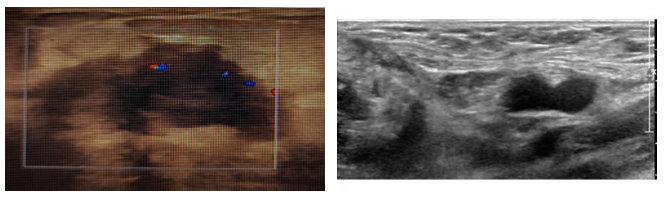

CT:提示右侧乳房未见明显的肿块,右侧腋窝淋巴结明显肿大;

图2. 胸部CT 2021.9.25

MRI:右侧乳腺肿块、结节,右侧腋窝肿大淋巴结,BI-RADS:5类。考虑右乳癌伴右腋窝淋巴结转移可能(2021-9-28)。

图3. 胸部MRI 2021.9.28